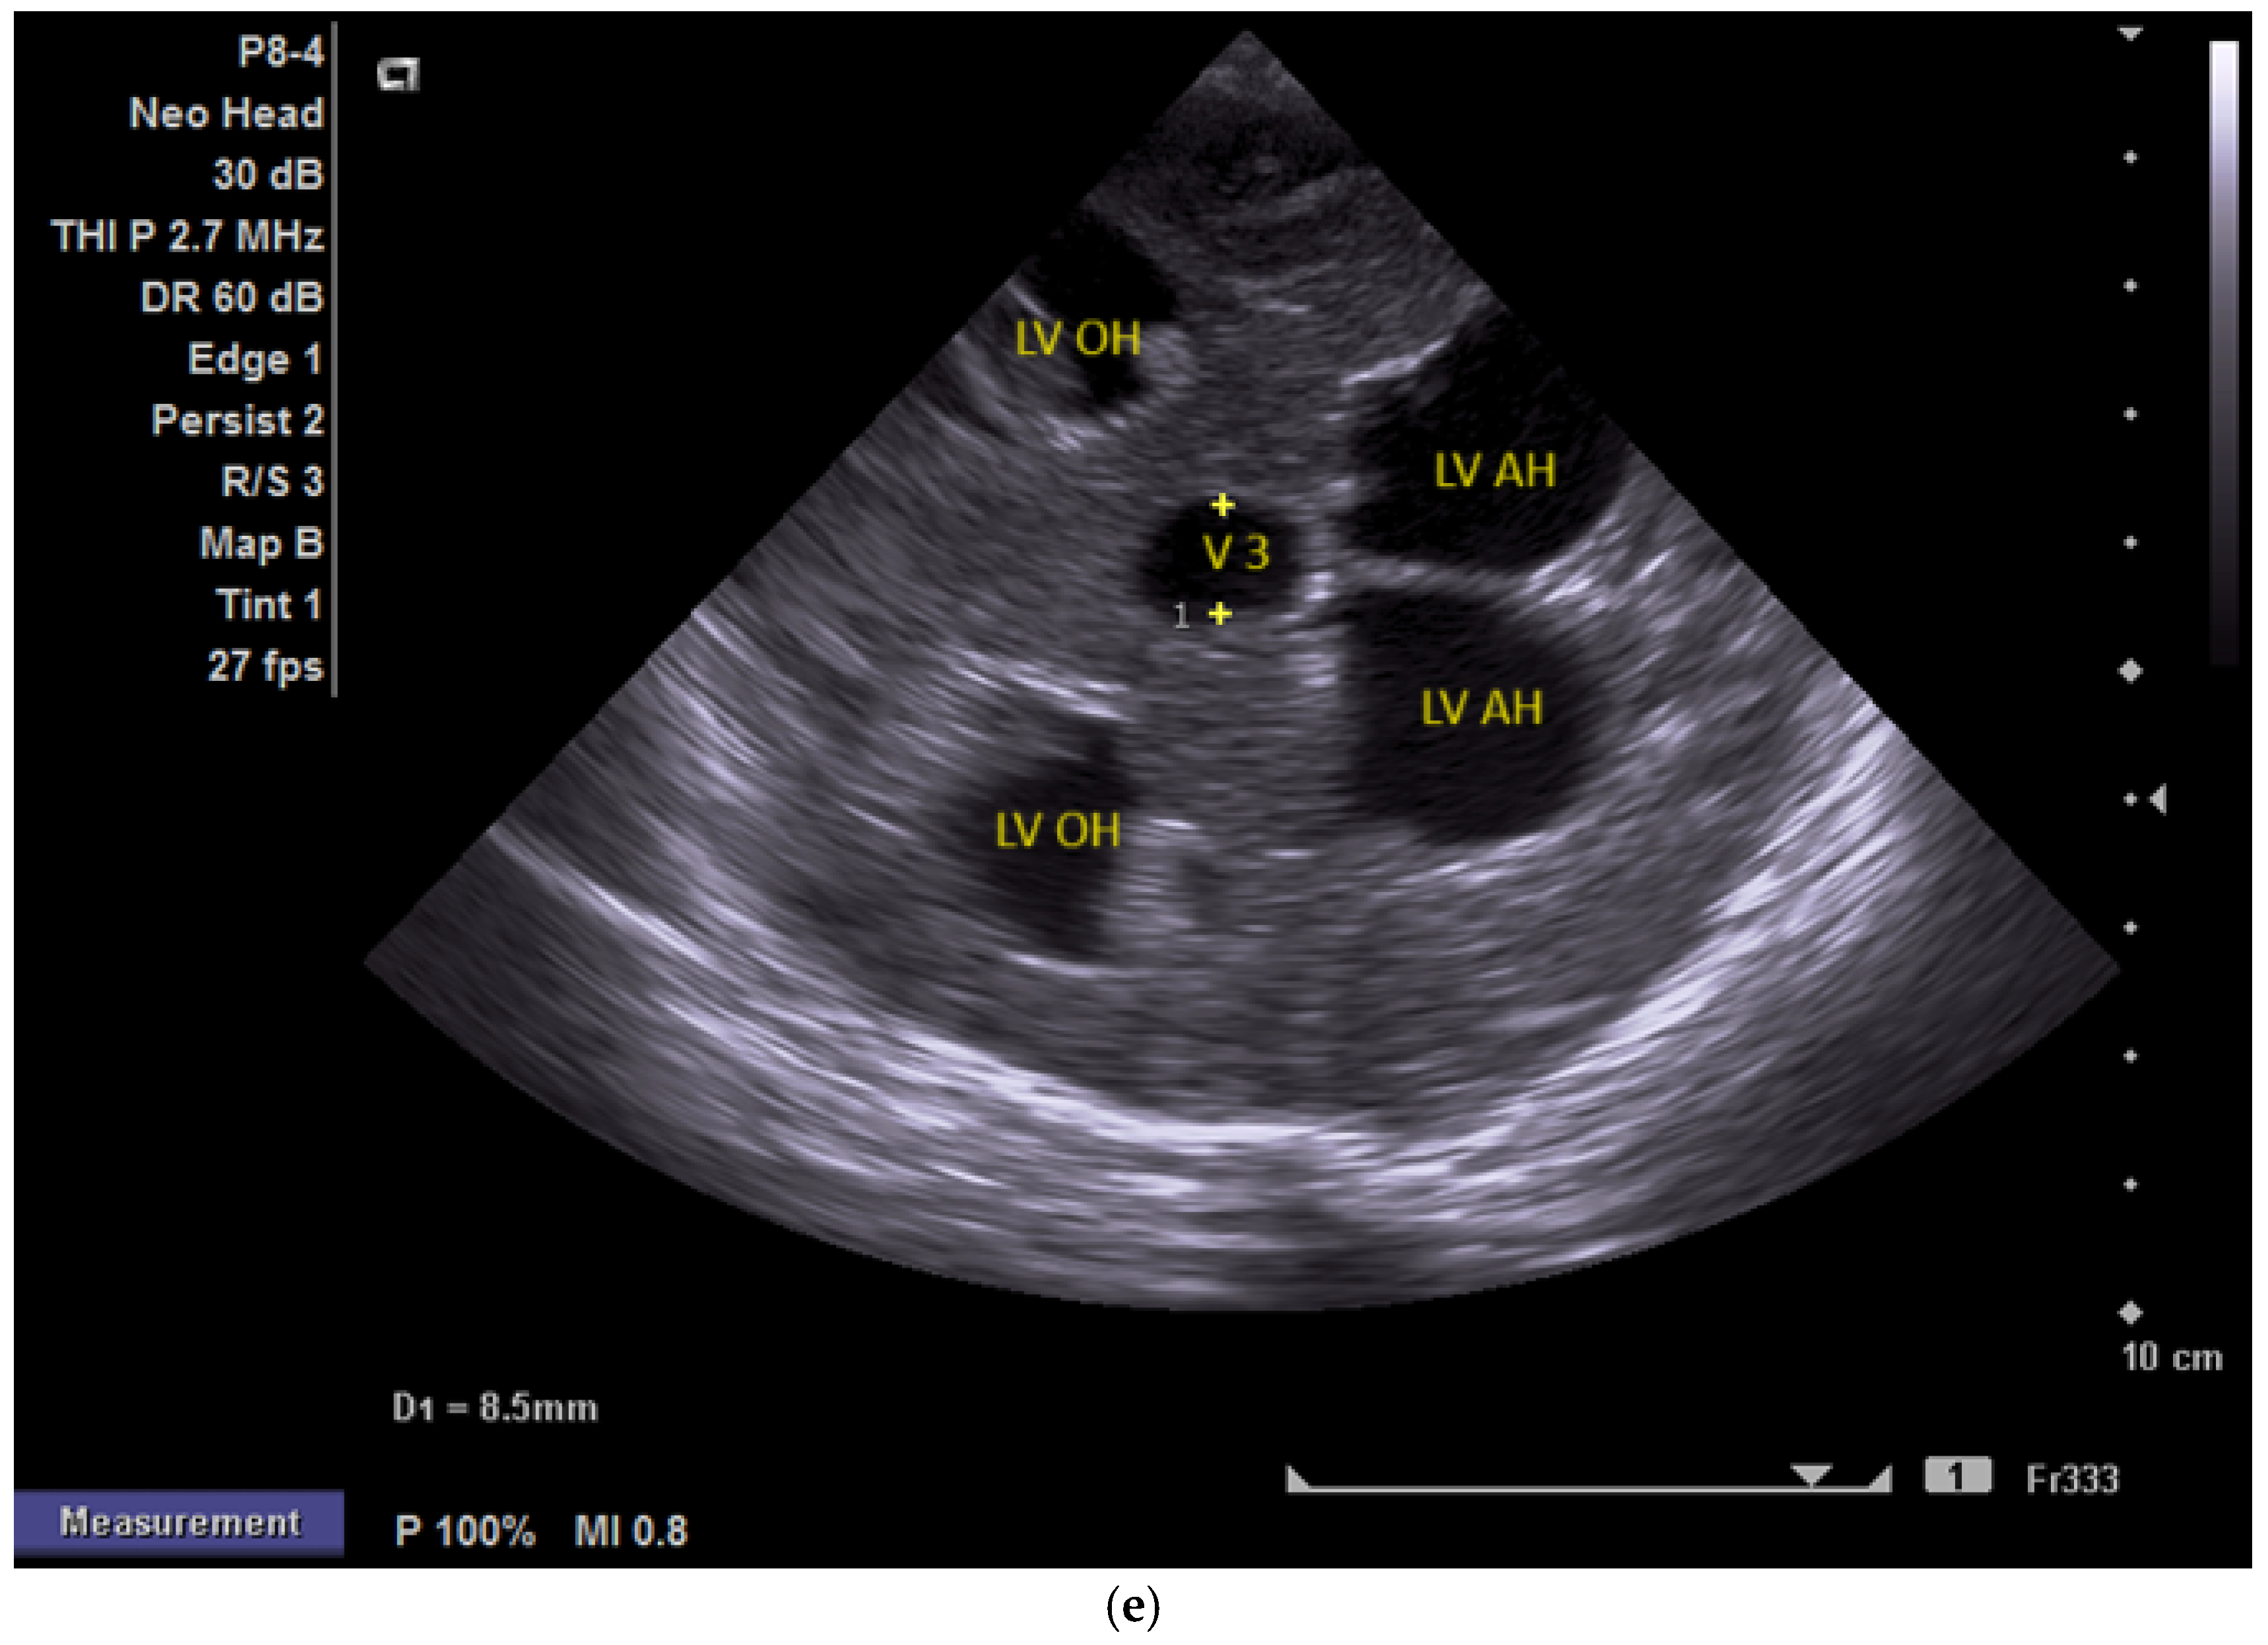

(a,b) MRI—T2 sequence. Sagittal view. Antenatal. Yellow arrows indicate the place of the suspected tumor (personal image collection). (c) Cranial ultrasound. Sagittal view. Up—enlarged left ventricle. D1—thamalo-occipital distance. Down—enlarged right ventricle. D1—thalamo-occipital distance (personal image collection). (d) Cranial ultrasound. Sagittal view. Enlarged third ventricle. Fourth ventricle is normal. D1, D2—measurements of the third ventricle (personal image collection). (e) Cranial ultrasound. Transtemporal view. Enlarged third ventricle. Sylvian aqueduct is not visible. D1—measurement of third ventricle. LV AH—lateral ventricle anterior horn. LV OH—lateral ventricle occipital horn. V 3—third ventricle (personal image collection).

After stabilization, the cranial ultrasound exam revealed enlargement of the lateral ventricles and third ventricle, with a normal fourth ventricle. There was no visualization of the Sylvian aqueduct, which raised the suspicion of aqueduct atresia or stenosis (Figure 5c–e). There was no improvement seen in the cranial ultrasound examinations that followed.